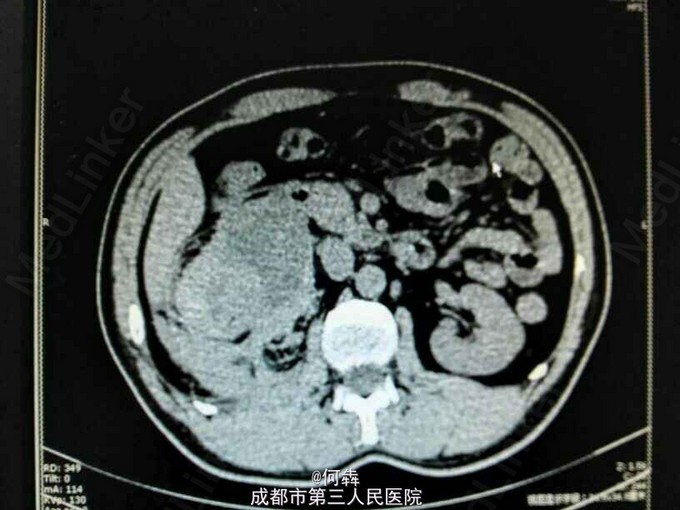

48岁男性,因“突发右腰痛1小时”入院,无血尿、外伤。既往无高血压、糖尿病。

右肾区扣痛阳性,余阴性。

右肾占位伴出血。入院后6天在全麻下行右肾部分切除术。术中冰冻及术后病检见图片